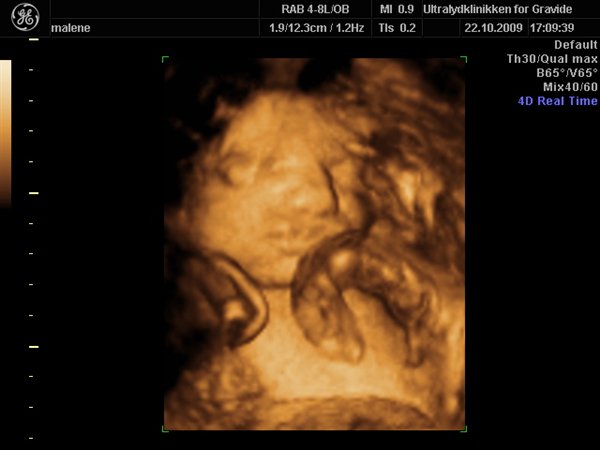

Jeg havde egentlig besluttet fra start af at jeg ville bestemt ikke smide penge efter en 3D scanning, men må indrømme jeg blev fristet

Så vi fik en hurtig tid i eftermiddags, og kom op og vinke lidt til den lille meget stædige prinsesse som vi så fint bekræftet hun er

Hun har allerede nu en masse hår på hovedet, og ligger meget dybt i bækkenet, så det var ikke muligt at få hele hovedet med, da man jo ikke kan scanne igennem knogler.

Hun var lige som hun skulle være, og vejer 1200 g

Vedhæftede fotos (klik for at se i fuld størrelse)